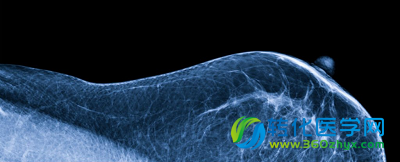

然而你可能没有发觉,女性的乳腺里也有大量的细菌存在,最近的一项研究表明女性乳腺中的微生物种群特征可能会影响其乳腺癌发病的风险。

不过,2014年一篇文章横空出世,向这一说法发出挑战。来自加拿大渥太华大学的研究者们发现人类的乳房中确实存在多种不同类型的菌群,它们能够刺激周围的免疫细胞从而维持乳房组织的健康环境。

为了进一步研究这一问题,研究者们希望搞清楚乳房中究竟存在那一类的细菌,以及乳腺癌女性与健康女性之间在这一方面是否存在差异。

他们分析了13名接受乳房肿瘤切除术或乳房切除术的良性肿瘤患者、45名恶性肿瘤患者以及23名健康女性的样本。结果显示,患有乳腺癌中的女性其组织中肠杆菌、葡萄球菌、杆菌等等的水平有明显增高,而这些细菌都是被证明能够造成人类细胞DNA双链断裂。

而那些健康人的样本中含有大量的乳球菌、链球菌等等。